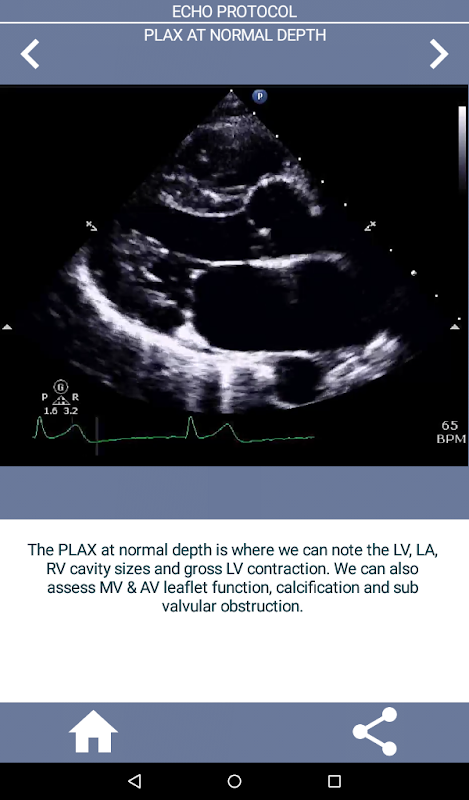

ابھی ایکو کارڈیوگرافی سیکھنا شروع کر رہے ہیں یا اس ایکو جاب انٹرویو کے لیے فوری ریفریشر کی ضرورت ہے؟ یہ ایپ آپ کو ایکو ٹیکنولوجسٹ کی مشق کرنے والے ایکو ٹیکنولوجسٹ کے نقطہ نظر سے فی الحال ایک بڑے ہسپتال میں استعمال ہونے والے مکمل TTE پروٹوکول پر تیز رفتاری کے ساتھ تیز رفتاری فراہم کرے گی جبکہ کارڈیک سونوگرافر کو ایک جامع، تفصیلی "کیسے کریں" گائیڈ لائن بھی فراہم کرے گی۔ . ایپ 90% سے زیادہ ویڈیو کلپس پر مشتمل ہے جس میں مناسب نظارے دکھائے گئے ہیں اور سب سے عام غیر معمولی کارڈیک پیتھالوجی (جیسے aortic stenosis) کو بھی دکھایا گیا ہے جس کا ایکو ٹیک ممکنہ طور پر سامنا کرے گا اور کیا کرنا ہے۔